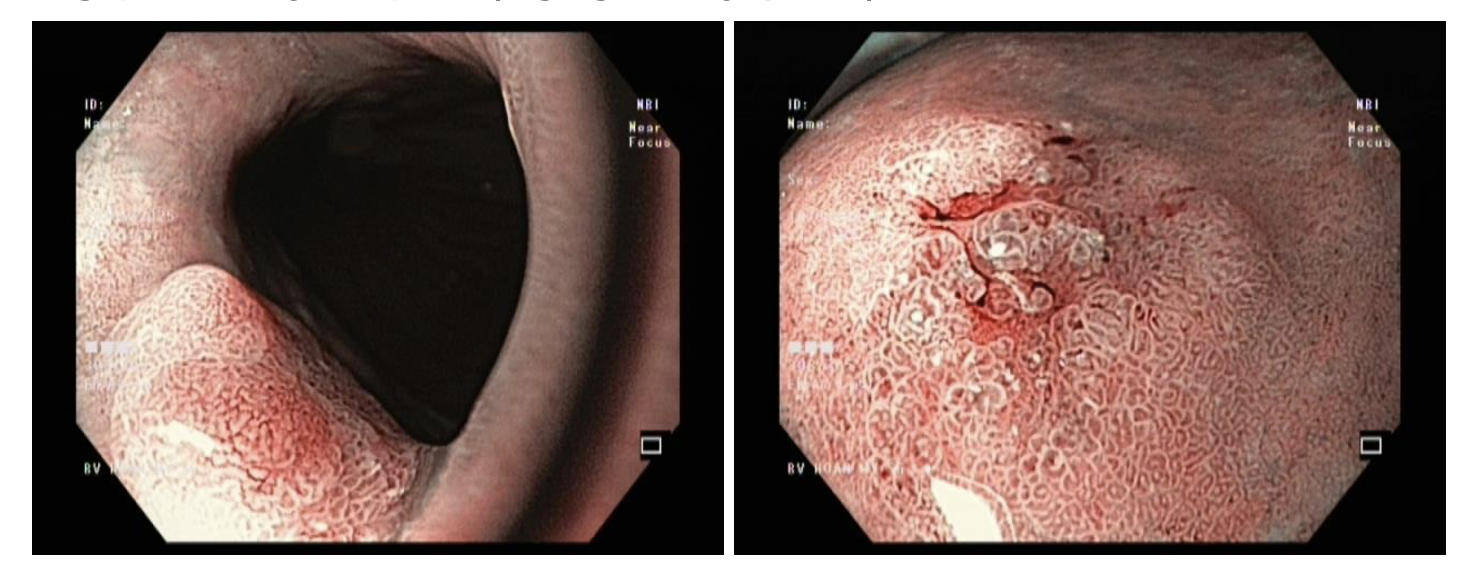

Thông qua hình ảnh nội soi ống tiêu hóa, bác sĩ phát hiện 02 tổn thương trong dạ dày, nghi ngờ ung thư ở giai đoạn sớm.

BS.CKI. Cao Văn Viễn, Đơn vị Nội soi Tiêu hóa, cho biết "Nghịch sản độ cao là một dạng tổn thương tiền ung thư nghiêm trọng. Các tế bào đã có những biến đổi bất thường rõ rệt và có nguy cơ rất cao sẽ tiến triển thành ung thư xâm lấn nếu không được loại bỏ kịp thời. May mắn cho trường hợp của bà Đ., các tổn thương được phát hiện khi vẫn còn ở giai đoạn sớm. Đây là những tổn thương được phát hiện ở giai đoạn mà các tế bào bất thường vẫn còn khu trú hoàn toàn ở lớp bề mặt (niêm mạc), chưa xâm lấn qua màng đáy để đi vào các lớp sâu hơn chứa mạch máu và bạch huyết. Việc phát hiện ung thư ở giai đoạn sớm giúp nâng cao đáng kể khả năng điều trị khỏi hoàn toàn. "